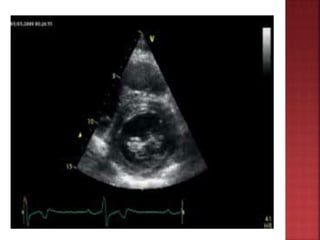

 M mode echo define ASH

 LV hypertrophy with septum >1.3times

posterior LV wall thickness

 Ground glass appearance of septum

 Spade shaped LV Cavity

 small lv cavity

 SAM of mitral valve

 septal immobility

 premature closure of aortic valve